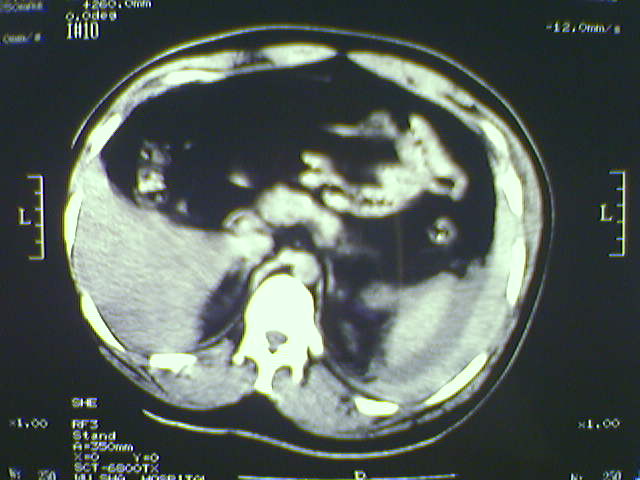

以下是引用lxq2000在2008-6-3 22:28:00的发言:[br]腹腔积液,腹壁软组织及左侧腰大肌肿胀建议mr检查。

以下是引用zjzjr在2008-6-3 21:01:00的发言:[br]腹腔积液+邻近软组织肿厚.考虑感染性病变可能性大.